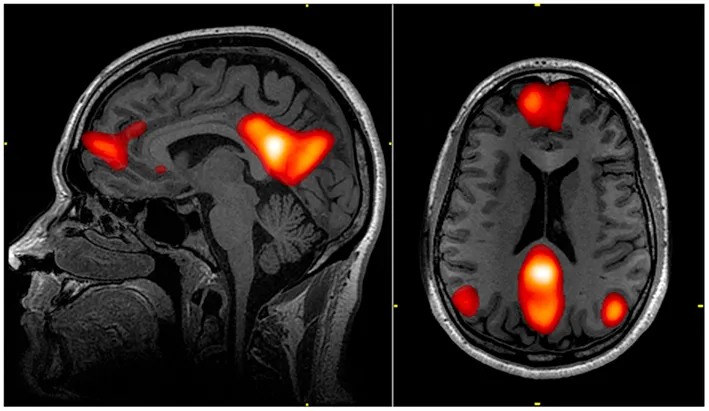

Rola "sieci trybu domyślnego" (DMN) i jej wyciszenie

Jednym z kluczowych odkryć w neuronauce psychodelików jest ich wpływ na tzw. sieć trybu domyślnego (ang. Default Mode Network, DMN). DMN to zespół obszarów mózgu aktywnych, gdy nie jesteśmy skupieni na zewnętrznym zadaniu odpowiada za myślenie o sobie, przeszłości, przyszłości, marzenia na jawie. Jest to obszar silnie związany z naszym poczuciem "ja", ego. Badania pokazują, że psychodeliki, takie jak psylocybina, znacząco obniżają aktywność DMN. To wyciszenie pozwala na tymczasowe rozpuszczenie granic ego, co może prowadzić do doświadczeń poczucia jedności ze wszechświatem, głębokiej introspekcji i poczucia transcendencji. Zmniejszona aktywność DMN wydaje się być neuronalnym podłożem dla wielu mistycznych i duchowych przeżyć.

- Psychodeliki mogą być potężnym narzędziem do indukowania głębokich doświadczeń duchowych, takich jak poczucie jedności czy transcendencja ego, często poprzez modulację aktywności sieci trybu domyślnego (DMN) w mózgu.